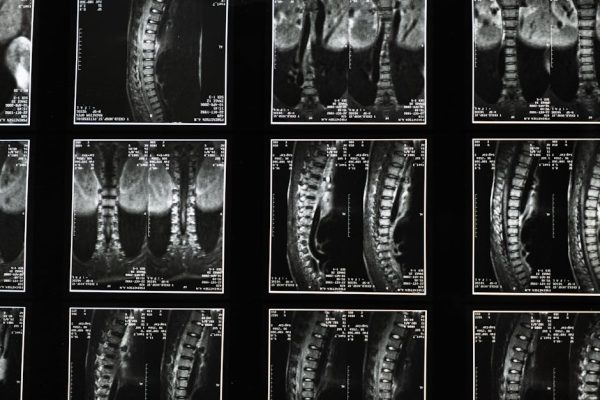

Understanding Surgical Options for Severe Sciatica: When Is It Considered?

IntroductionSurgery for sciatica is never a first-line treatment. It is reserved for a small percentage of patients whose severe symptoms fail to resp…

IntroductionSurgery for sciatica is never a first-line treatment. It is reserved for a small percentage of patients whose severe symptoms fail to resp…